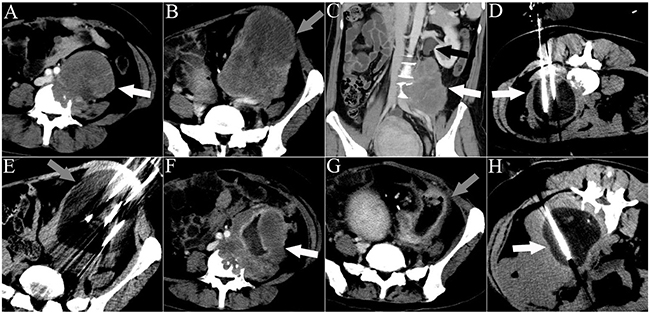

Figure 4: CT images of a 33-year-old man who underwent 3 sessions of cryoablation for 2 RPSs. The patient presented with abdominal pain for 45 days. The white arrowheads indicate lesion 1. The gray arrowheads indicate lesion 2. The black arrowhead indicates ureteral dilation. The white lines indicate the cryoprobes. The dark area around the cryoprobe is the ice-ball. A. A cross-sectional contrast-enhanced CT image illustrating lesion 1 with spinal invasion. B. A cross-sectional contrast-enhanced CT image illustrating lesion 2. C. A coronal contrast-enhanced CT image illustrating lesion 1 with ureter invasion. D. The first session of cryoablation for lesion 1. E. The second session of cryoablation for lesion 2, performed 1 month after the first session. F, G. Cross-sectional contrast-enhanced CT images acquired 1 month after the second session of cryoablation illustrate necrosis of both lesions and significant shrinkage of lesion 2. H. The third session of cryoablation for lesion 1.